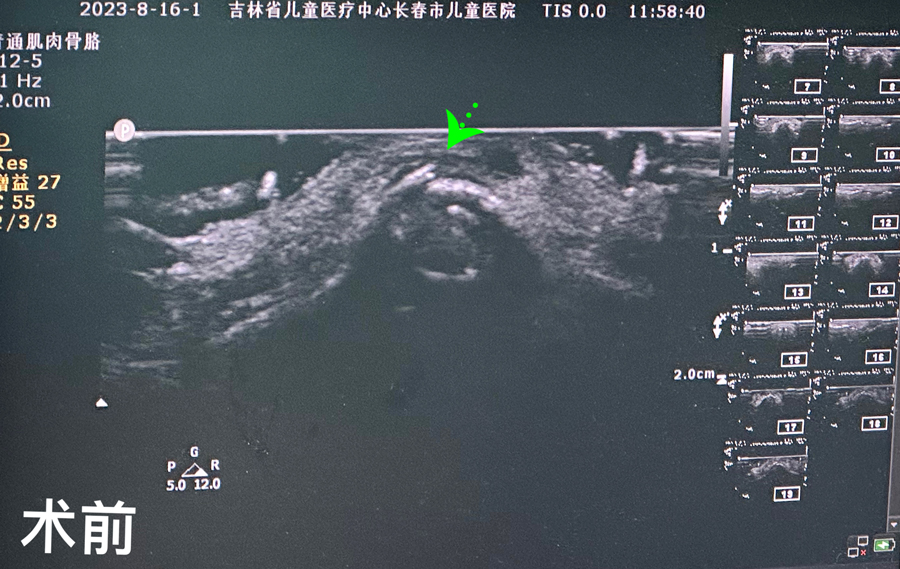

8月15日,彬彬家长在辗转多家医院后,听说德州扑克游戏网 有鼻骨骨折复位新技术,立即带彬彬赶到医院。此时,距离彬彬鼻骨骨折已经过去一周了。就诊时,彬彬鼻部肿胀已经消退了,能看到他的鼻梁是向左侧偏曲的,妈妈特别希望孩子的鼻梁能恢复到从前高挺、居中的状态。国家儿童医学中心、北京儿童医院耳鼻喉头颈外科常驻专家、德州扑克游戏网 副院长张薇,德州扑克游戏网 耳鼻喉科主任李莉萍为其进行鼻部检查,并结合鼻骨CT全面评估后,决定采用超声引导下鼻骨骨折复位术,以实现精准复位,使彬彬的面容不受影响。8月16日,张薇副院长、李莉萍主任及手术室、麻醉科医护人员组成手术团队,为彬彬进行手术。术中,医生在超声引导下应用复位器对游离骨片进行复位调节,使错位的鼻骨重新连续。10分钟后,手术顺利完成,复位后的鼻子外观无畸形。术后,彬彬接受抗感染治疗48小时,情况稳定,顺利出院。

相比较传统凭经验及手感的鼻骨复位术,超声引导下的手术复位能更精准定位到损伤部位,如医生的“透视眼”,实现手术可视化,使医生在术中可准确看到鼻骨断端的对合情况,在“精准、微创、美观”上得到极大优化和提升。患儿无伤口、恢复快。术前和术后鼻骨错位及对合情况B超均有图片准确显示,让家长也能看明白,患儿和家长的心理负担明显减轻不少,改善了就医体验。